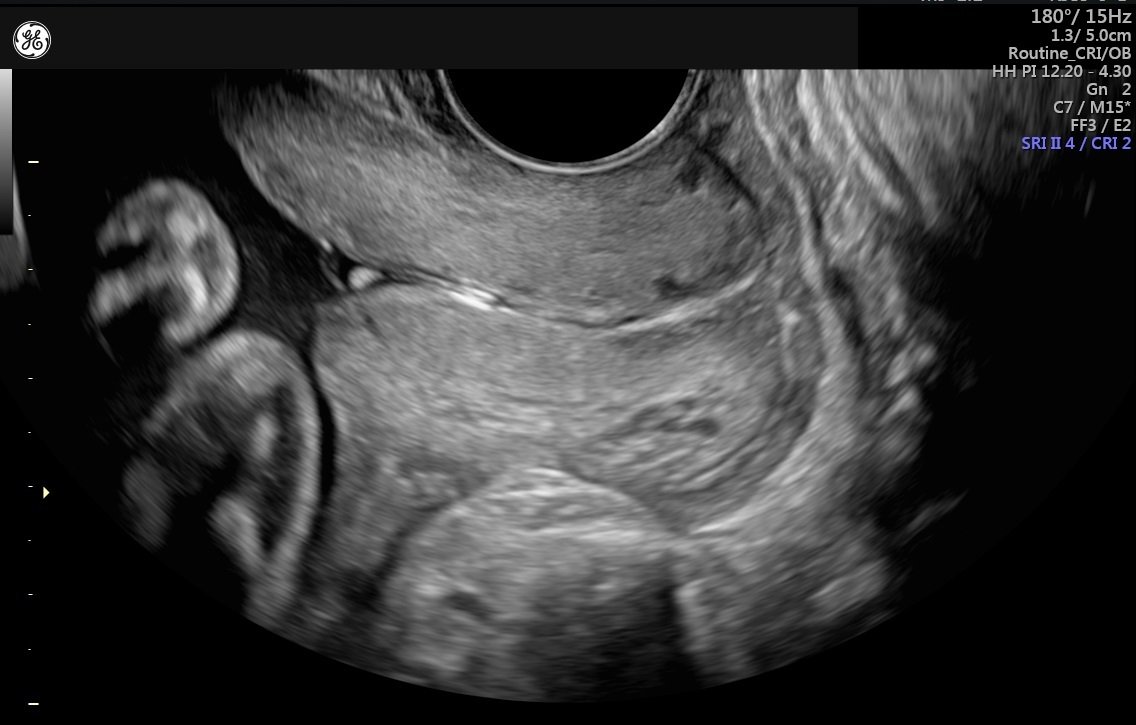

This scan is typically performed transvaginally for the most accurate results.

- Done using a transvaginal ultrasound probe

- Provides precise cervical measurements in millimeters